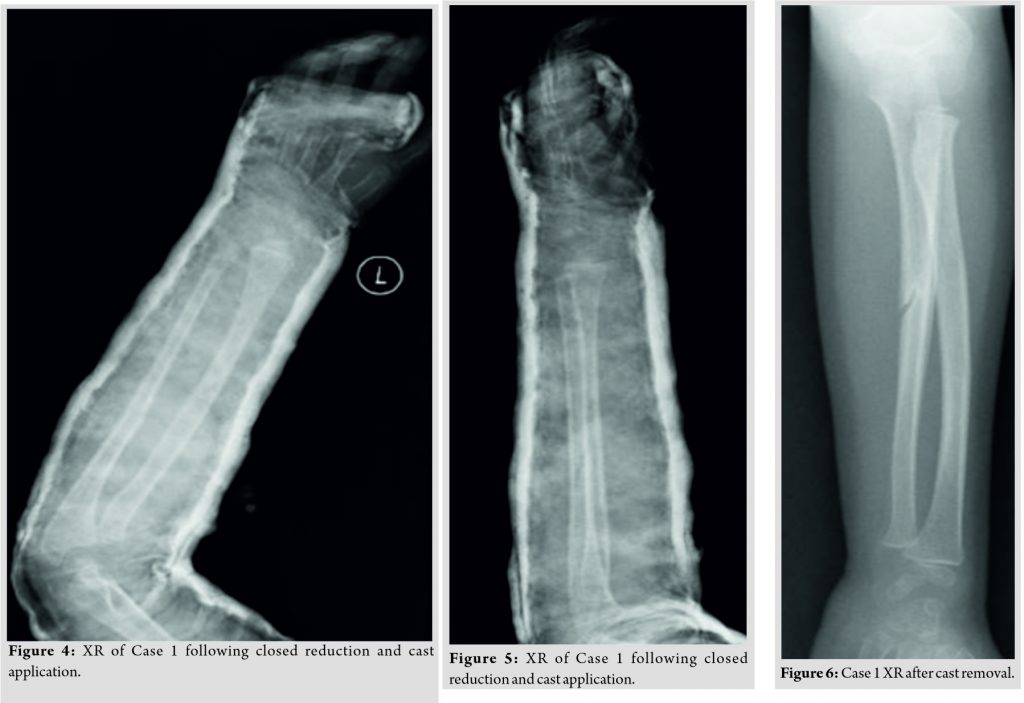

The patient was admitted for further treatment and consented for closed reduction under general anesthesia with the possibility of internal fixation versus open reduction and internal fixation. Intraoperatively, the patient was placed supine with the left arm on the arm board and was draped with strict aseptic technique due to the possibility of converting to open reduction. The traction-countertraction method was used to obtain reduction and slight pressure on the radial head to reduce it in place. The radial head was reduced and after a trial of range of motion and intraoperative fluoroscopy it was found to be stable, the patient was placed in an above elbow cast in slight hyperflexion to maintain reduction (Fig. 4, 5).

The patient was kept for 24 h postoperatively to monitor the neurovascular status, she was discharged and given follow-ups at 2, 4, and 6 weeks. The cast was removed 6 weeks post-operative (Fig. 6, 7) and the patient experienced slight elbow stiffness as expected. The patient was not given a formal physical therapy referral and the family was instructed with home exercises and where educated to advocate the patient to use his injured limb, at 12 weeks, the patient had full range of motion of the left arm and elbow and was discharged.